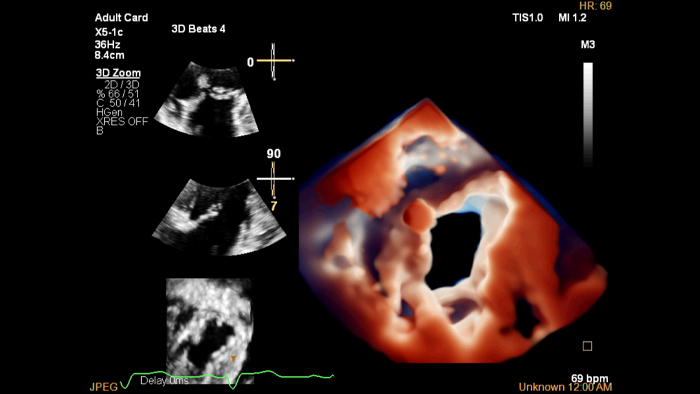

EPIQ CVx

The EPIQ CVx is a dedicated cardiac ultrasound solution which brings significant advancements in functionality. This helps you deliver better care through higher processing power, exceptional imaging with more clarity & sharpness, improved exam efficiencies, complemented by the proven, robust quantification capabilities of Ultrasound Workspace.

Professor Alex Lee, Prince of Wales Hospital, Hong Kong, China

Photorealistic imaging in 3D echocardiography

A virtual light source highlights structures and facilitates depth perception for enhanced interpretation of heart disease images.